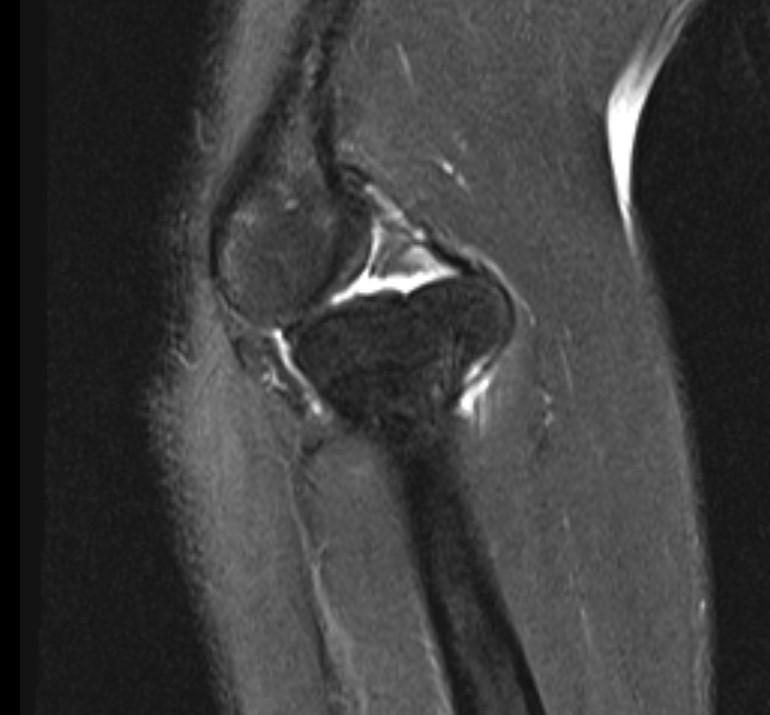

Case 1. Missed Monteggia, injury 6 months ago

Case 2. Chronic Monteggia with deformed radial head